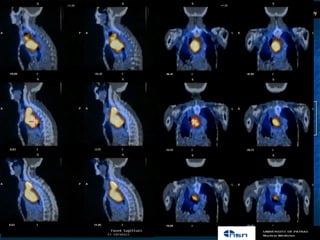

Πενίπηςζε –Νμ 9

Γοκαίθα, 57 πν.

MIBI EARLY      MIBI LATE                                2.

1.

PERTECHNETATE   SUBTRACTION

Α. Γπίπεδε απεηθόκηζε

δηπιήξ θάζεξ θαη

αθαηνεηηθή ηεπκηθή

ανκεηηθή

B. SPECT/CT δείπκεη δύμ ύπμπηα- αζαθή εονήμαηα

Όπςξ θαίκεηαη ζηηξ ζέζεηξ πμο δείπκμοκ ηα βέιε